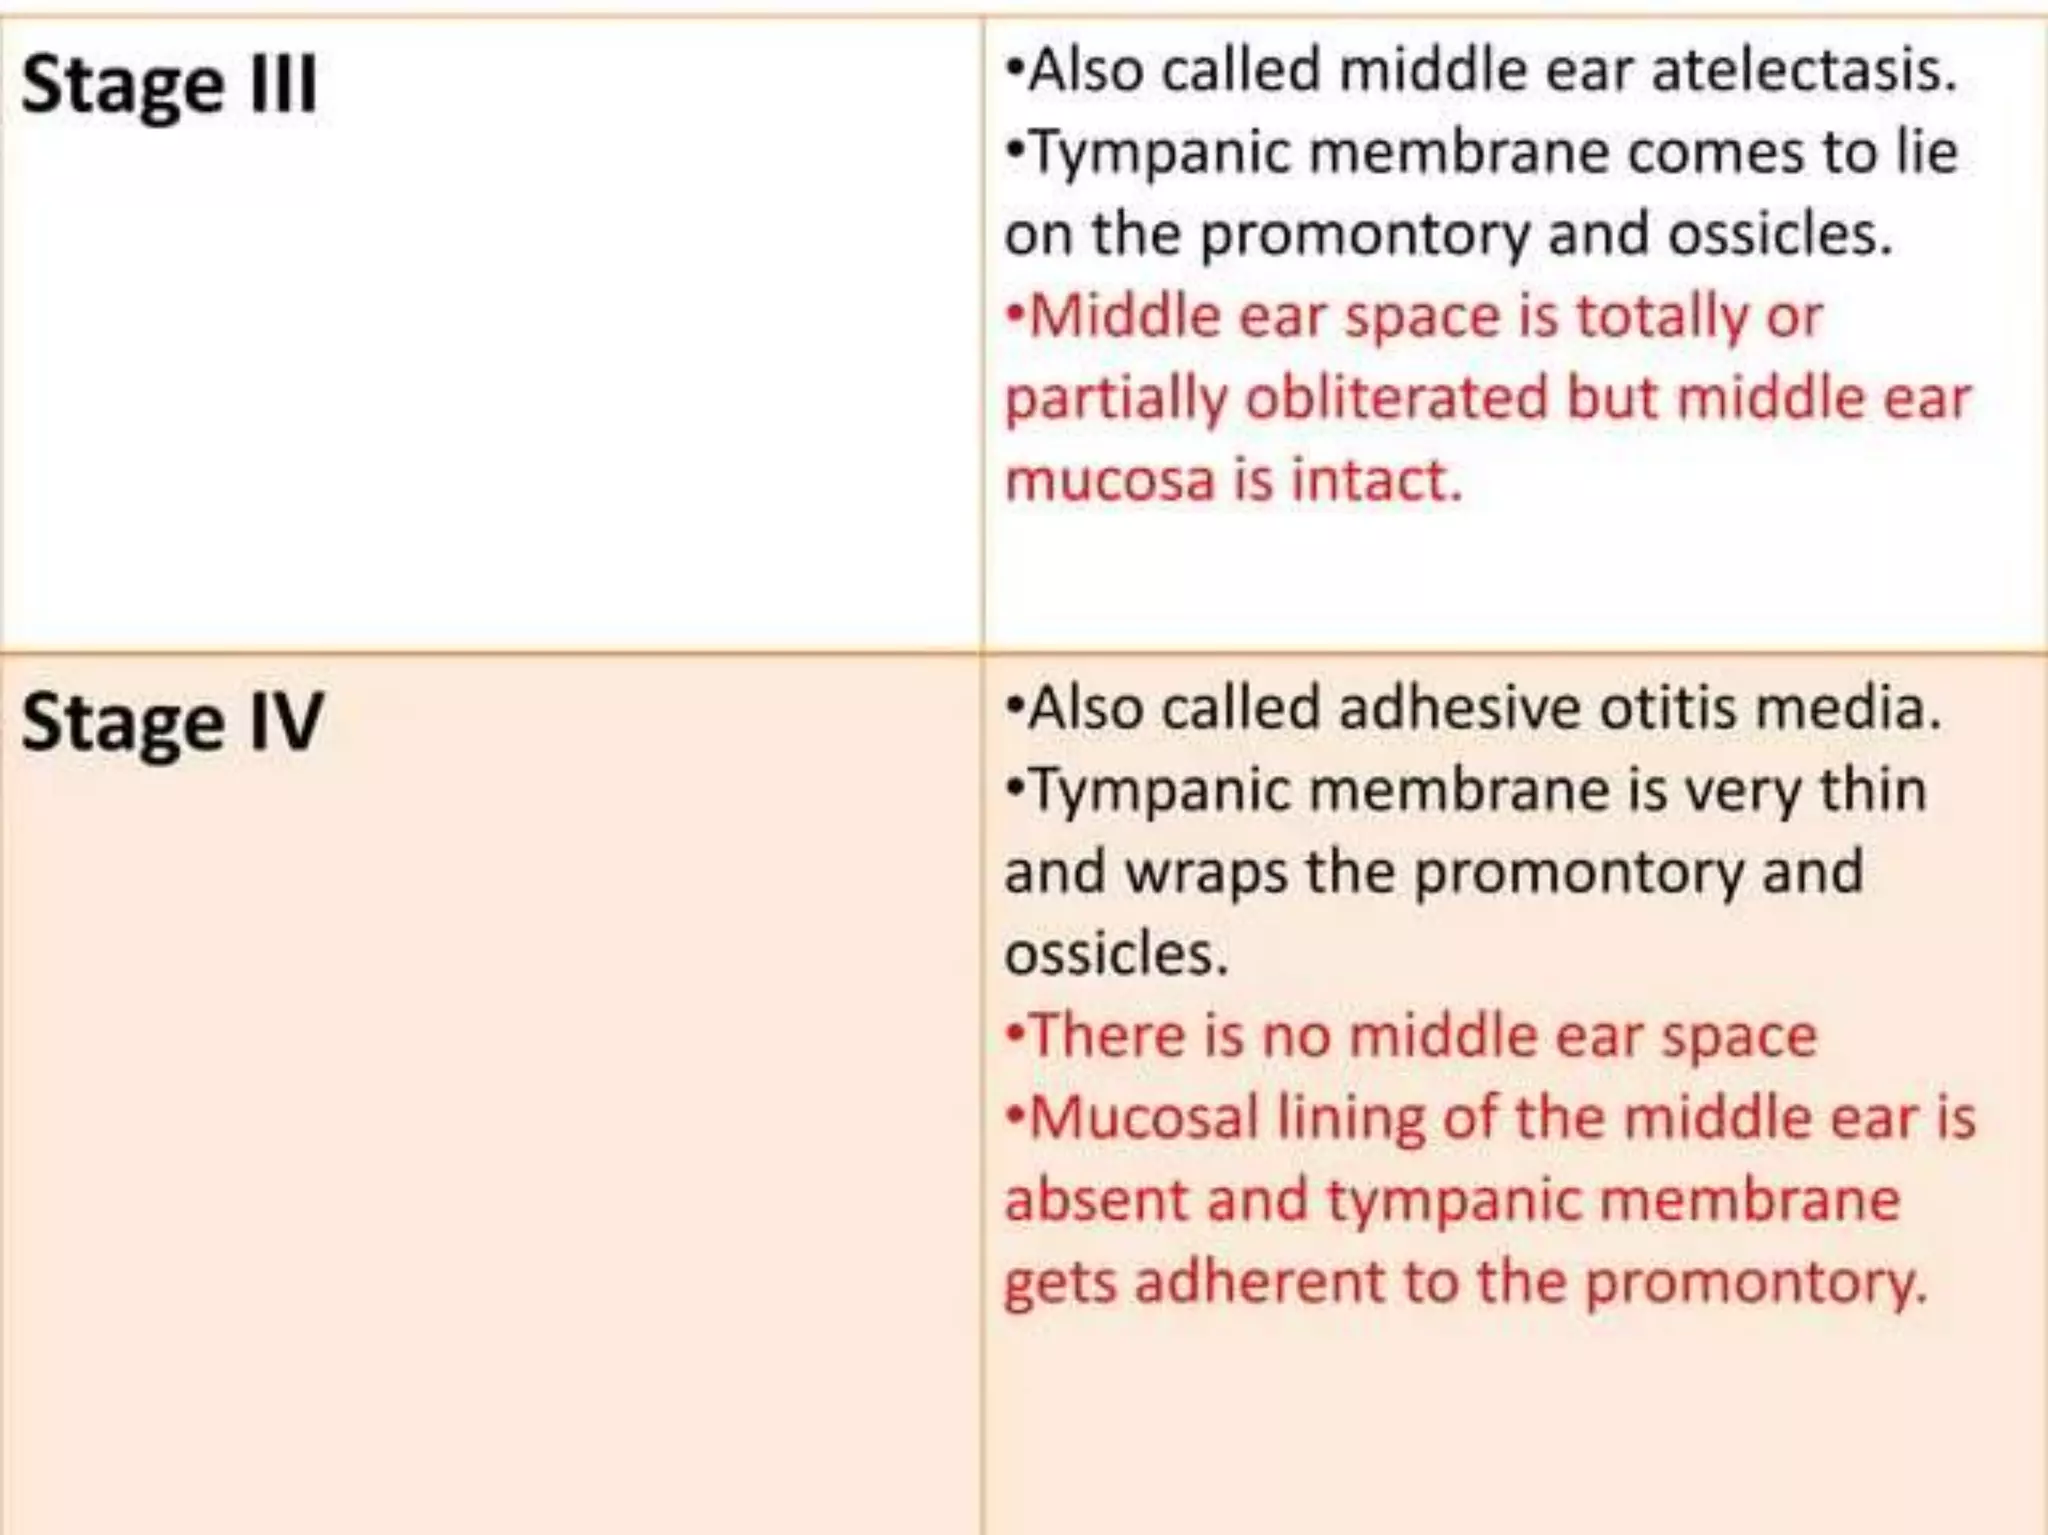

Chronic otitis media is a chronic inflammation of the middle ear and mastoid cavity that presents with recurrent ear discharge through a perforated eardrum. It has several subtypes depending on the state of the eardrum perforation and epithelium. It can be caused by prior acute otitis media, genetics, environment, eustachian tube issues, gastroesophageal reflux disease, craniofacial abnormalities, or immune deficiency.